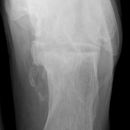

Calcaneus